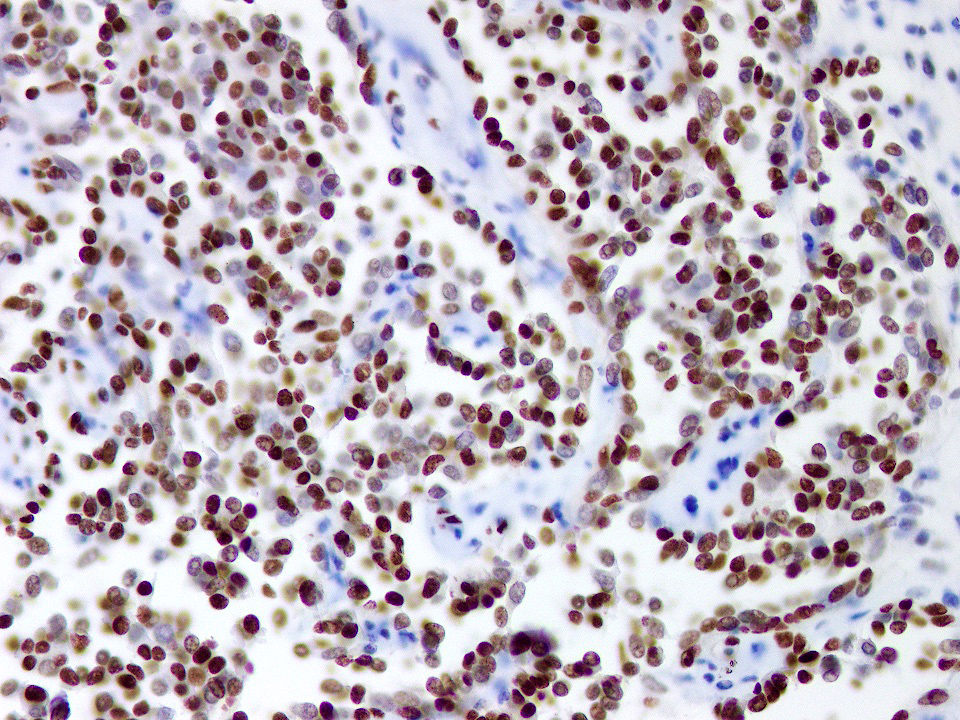

Positive stains

- ERG: nuclear staining

- PROX1: nuclear staining (Am J Surg Pathol 2012;36:351)